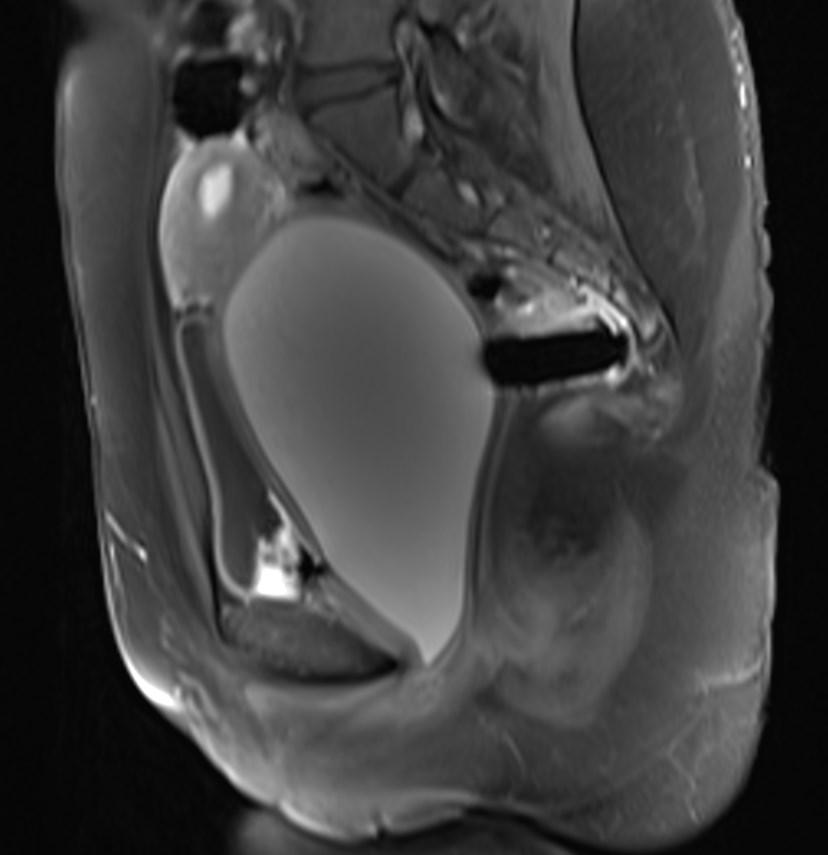

MR images showed hemorrhagic fluid in a distended vagina. The uterine cavity is not dilated.

In haematocolpos, there is accumulation of menstrual blood in the vagina in the setting of an anatomical obstruction, usually an imperforate hymen. When there is concurrent uterine distention, the term haematometrocolpos is used.